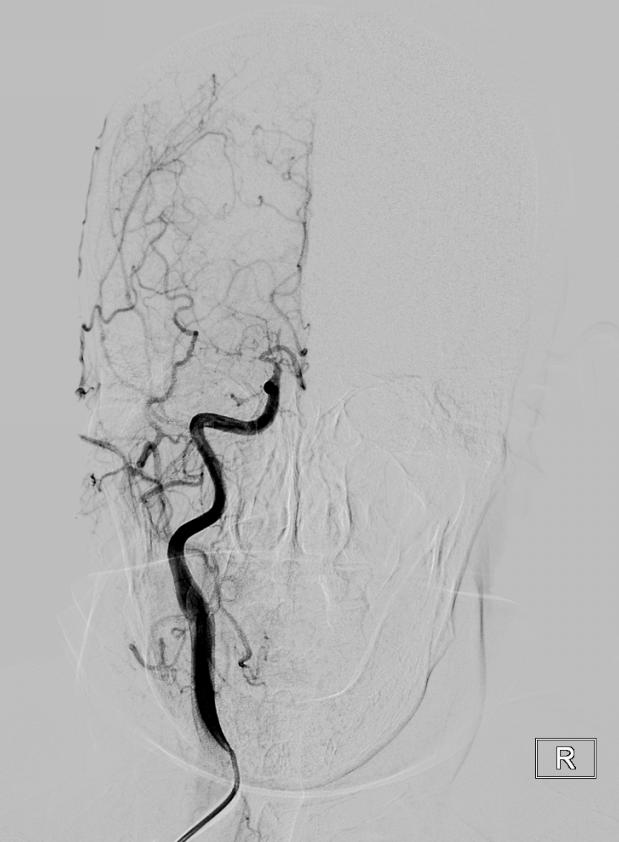

流行病学研究基本上将脑卒中分为出血性卒中和缺血性卒中两大类。出血性脑血管病包括:颅内动脉瘤、脑血管畸形、高血压脑出血等。

缺血性脑血管病包括各种病因如颅内动脉狭窄、颈动脉狭窄、椎动脉狭窄、锁骨下动脉狭窄、烟雾病(Moyamoya病)、动脉粥样硬化疾病或心源性疾病导致的脑缺血。在我国急性缺血性脑卒中是最常见的卒中类型,约占脑卒中的69.6%~70.8%,在空间分布上有北方高、南方低的趋势,这与高血压患病率的空间分布几乎一致。急性缺血性脑卒中的处理包括早期诊治、早期预防再发(二级预防)和早期康复。随着医疗技术水平的提升及医学材料科学的进步,缺血性卒中的治疗由早期的静脉药物溶栓治疗发展为血管内溶栓、急诊支架取栓等多种治疗方式。而对于预防缺血性脑卒中事件的发生,颈动脉内膜剥脱术、脑血管搭桥手术、责任血管的球囊扩张加支架置入术等多种治疗方案亦发挥着不可替代的作用。